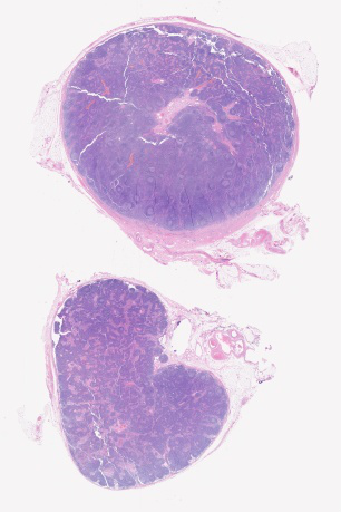

Pathology Image Library

ARUP Laboratories®